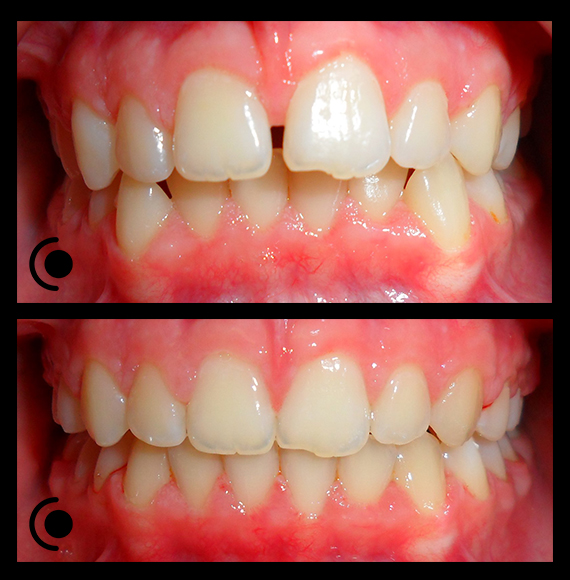

O našoj kvaliteti najbolje govore naši rezultati!

Centar za ortodonciju Petra Džapo